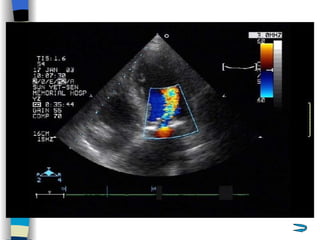

Doppler  echo Allows calculation of the aortic valve gradient Estimate the severity of the stenosis <  30 mmHg  Mild AS MPG  30~50 mmHg  Moderate AS > 50 mmHg  Severe AS  Color Doppler flow imaging is helpful in the detection and determination of the severity of any accompanying aortic regurgitation

Echocardiography   Confirm diagnosis, estimate severity, identify the cause 2-D echo:  Structural changes  of the valve leaflets and/or aortic root M mode echo:  Diastolic fluttering  of the anterior leaflet of the mitral valve is an important echocardiographic finding in AR Serial assessments of LV size and function Doppler echo:  Sensitive, accurate noninvasive technique for detecting AR LVOT diastolic  regurgitant  jet , estimate the severity of AR Cardiac catheterization Quantify the severity of AR Evaluate the coronary and aortic root anatomy

Doppler echoAllows calculation of the aortic valve gradient Estimate the severity of the stenosis < 30 mmHg Mild AS MPG 30~50 mmHg Moderate AS > 50 mmHg Severe AS Color Doppler flow imaging is helpful in the detection and determination of the severity of any accompanying aortic regurgitation